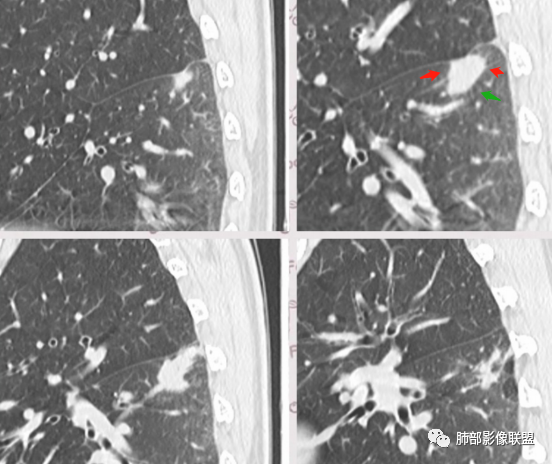

3、卫星灶与“蘑菇兄弟”:诊断隐球菌时,建议找卫星灶,卫星灶可以在遥远的地方。可以是遥远地方的微小结节——“小蘑菇兄弟”。有些远处的卫星灶,通常是不规则饱满实性的,晕征不明显。隐球菌的卫星灶非常“隐”,但发现率高达60%多,诊断价值高。

4、卫星灶距离远的原因:隐球菌卫星灶常很远,推测:一次空气来源隐球菌感染进入双肺多处,部分定居繁殖;距离近的隐球菌“蘑菇兄弟”常常是二次感染。

5、周围毛刺纤维、边缘形态等:坏死包裹会使得结节变圆;结节多缺乏明显的分叶征,缺乏局部突出生长能力;如果出现分叶,是由多处肉芽肿中心形成。没有坏死的局限化,结节只是凑合在一起,常呈方形征;毛刺进入晕区(概念源自南边老师),毛刺较短、较软;周围的晕吸收后,会留下不规则边,外面常残留丝状条索;收缩力较弱,临近胸膜对胸膜牵拉不明显。

6、隐球菌的毛刺消失于晕区的解释:隐球菌结节周围有间质淋巴细胞增多,肉芽肿性炎延伸,以及纤维组织增生,形态并不规则,不是因为收缩力。